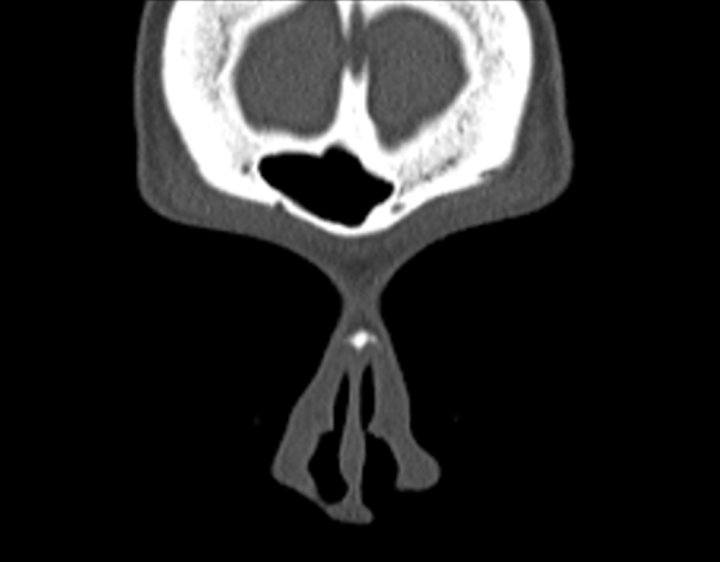

Click any image for labels.